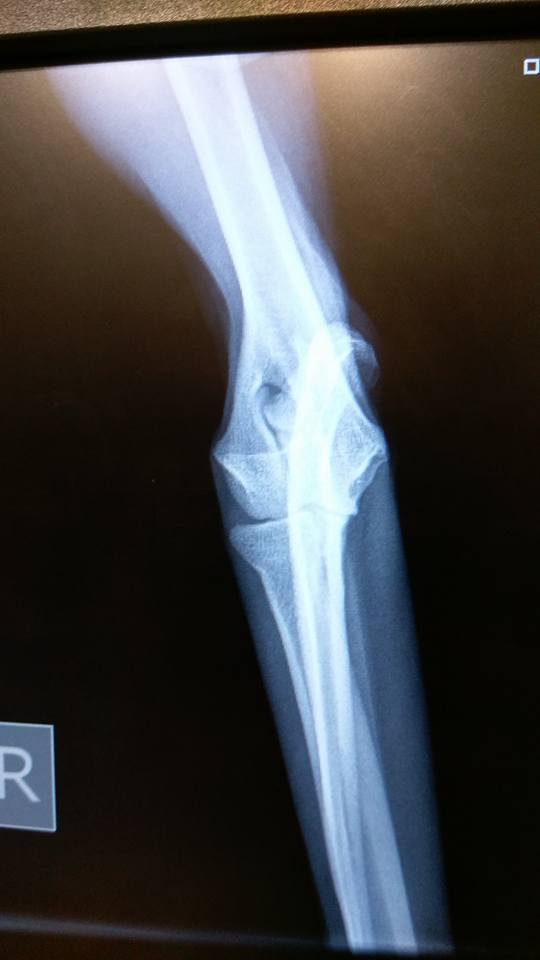

As you can see his bone is going off at an angle. The plan is to cut a wedge from his ulna, realign the bone with titanium plates and then use stem cell therapy in his elbow joint as it has significant collapse.

He has a host of problems but now needs elbow surgery.As you can see his bone is going off at an angle. The plan is to cut a wedge from his ulna, realign the bone with titanium plates and then use stem cell therapy in his elbow joint as it has significant collapse.